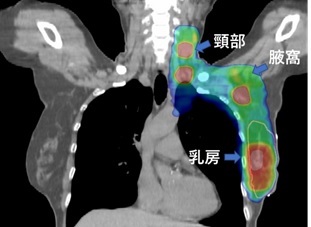

乳がん

乳がんの温存手術後に、局所の再発予防を目的として乳房全体に放射線治療を行います。がんが大きかった場合やリンパ節転移があった場合などでは照射する範囲を広げることもあります。

乳房を全摘出された方でもがんが大きかった場合やリンパ節転移があった場合などでは放射線治療を行います。

照射線量は50~60Gy、照射期間は5~6週間程度です。

早期がんの方では1回の照射線量を増やして照射回数を25~30回から16~20回程度に減らす寡分割照射を積極的に採用しています。

また、左乳がんの場合、通常の照射法では左乳房に近接する心臓に悪影響を与えるおそれがあります。当院では、心臓への影響を避けるため深吸気息止め照射という照射法を用いています。

乳がんで乳房温存手術後。再発を防ぐため同側の乳房全体に照射。

左乳がんの場合、従来の照射法(左図)では近接する心臓がわずかだが照射される。

深吸気息止め照射法(右図)を用いると心臓が照射されなくなることが多い。

腋窩リンパ節転移が多い場合、リンパ節再発しやすい首も含めて照射。